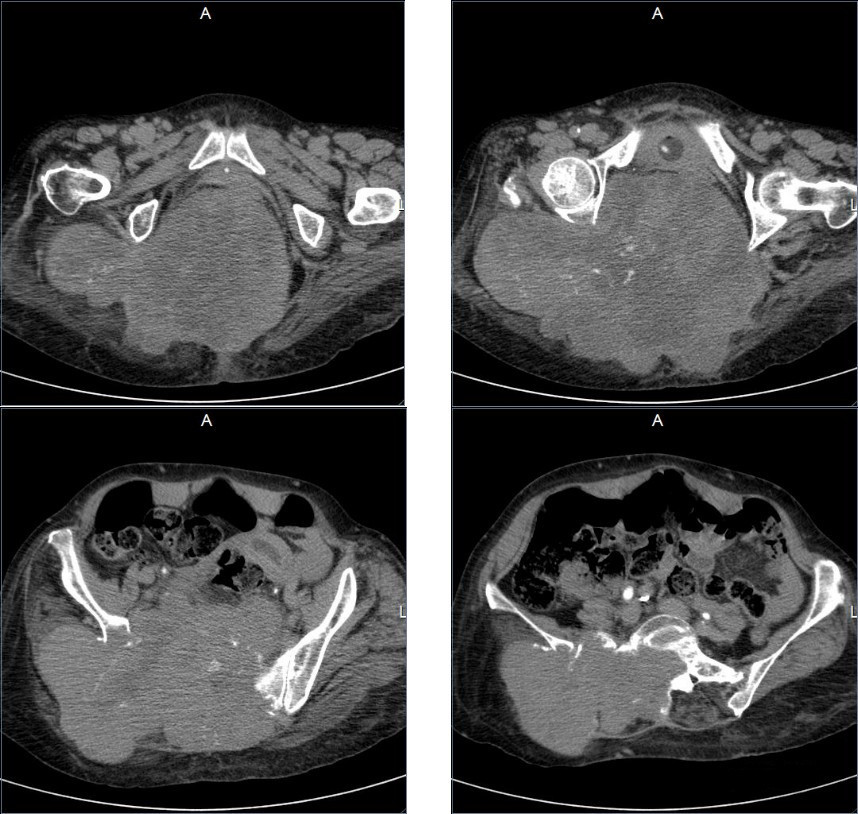

Mujer de 52 años, antecedente de carcinoma papilar de tiroides.

Antecedente de carcinoma papilar de tiroides

Padecimiento actual caracterizado por presencia de tumor en glúteo con destrución de iliaco y sacro

Cordoma